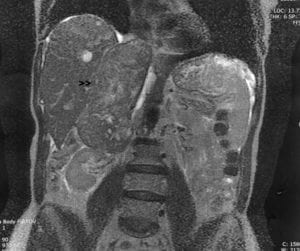

The procedure, laparoscopic power morcellation, can spread malignant tissue – if any is present in the patient – beyond the uterus and throughout the pelvic region, endangering her lifespan.

Power morcellators enable laparoscopic surgeons to break apart the uterus into tiny bits so the tissue can pass through a narrow port via a small incision in the abdomen. The problem arises when the tiny bits of tissue escape the port and spread into the body.